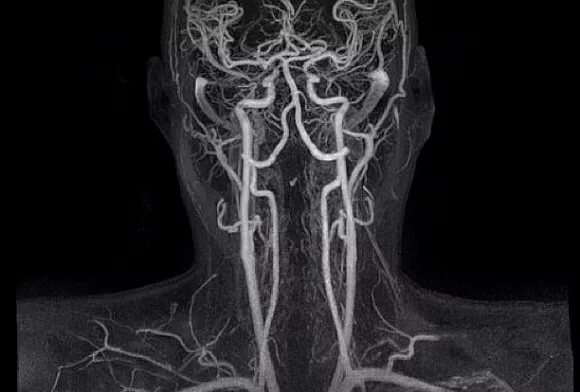

Непосредственно процедура сканирования длится не более 10 минут. Все это время пациент лежит в камере томографа на специальном столе, который поднимается и опускается, позволяя аппарату делать снимки с разных ракурсов. От диагностируемого требуется соблюдать спокойствие, выполнять команды врача, подаваемые по громкой связи, и сообщать медработнику о любых изменениях в самочувствии. Компьютерная программа, управляющая работой томографа, по ходу скрининга выстраивает на основании серии снимков полноценную трехмерную модель сосудистого русла шеи и головы, на которой видны все основные и периферические ветви. Эти данные оценивает врач-рентгенолог и в своем заключении отмечает любые выявленные аномалии. Такая подготовка результатов обычно занимает около часа.